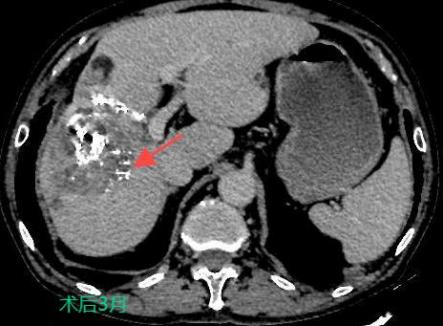

三、肝癌的介入治療

TACE/HAIC:經(jīng)肝動(dòng)脈灌注化療栓塞(TACE)、肝動(dòng)脈內(nèi)灌注化療藥物(HAIC)是在不開刀暴露腫瘤病灶的情況下,在皮膚上做直徑幾毫米的切口,在影像設(shè)備的引導(dǎo)下,導(dǎo)絲和導(dǎo)管插入肝臟腫瘤血管,注入栓塞劑和化療藥物使肝臟腫瘤內(nèi)化療藥物濃度提高,并減少全身的藥物總濃度,達(dá)到提高化療效果并減少毒副作用的目的。對于無法手術(shù)切除的巨塊型肝癌、肝內(nèi)多發(fā)肝癌病灶、肝癌結(jié)節(jié)破裂出血有良好的治療效果。

癌的介入治療